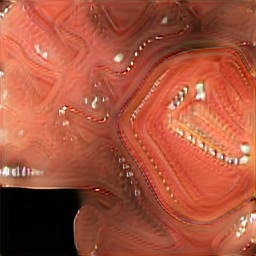

In Fig 7, we provide a visual comparison between pure generated synthetic images and style transferred images ( = ). Samples with the style transfer ratio are not depicted here because it is difficult to see the differences visually. The first column of Fig 7 shows the real images used as content images to transfer styles. The rest of the images in the first row of each image shows synthetic images generated from SinGAN-Seg before applying the style transferring algorithm. Then, the images in the second row in the figure show the style transferred synthetic images. Differences of the synthetic images before and after applying the style transfer method can be easily recognized from images of the second reference image (using and rows in Fig 7).